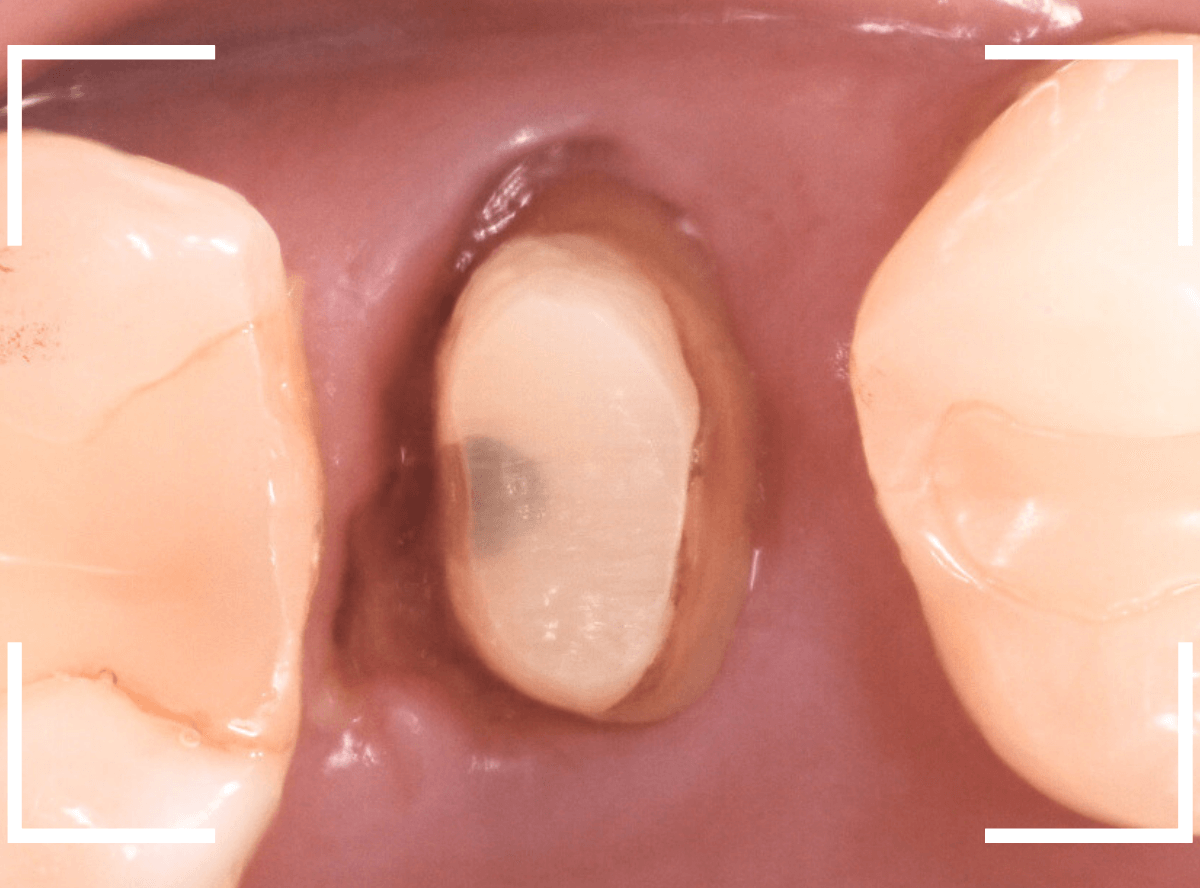

さし歯を入れるスペースがない!

一番奥の歯が土台(コア)の治療までで中断してしまってる患者さんの例です。

本来であれば、この上にさし歯を作らなければいけないのですが、この時点でかみ合ってしまい、さし歯を作ろうにも作りづらい状況でうやむやのうちに治療中断になってしまったようです。

まず、土台の治療をしてから時間が経過していることと、不適合になっている事から、外して中を調べます。

すると、土台の中で虫歯にもなっていました。

(〇部の赤い部分)

こういった事は、レントゲン写真でもよくわからない事が多く、土台を外す治療は本当に神経を使います。

今回は、歯肉の中まで歯が欠損しているので、このまま土台とさし歯を作り直しても、いい結果にはなりません。

患者さんに状況を説明し、歯の周りの歯肉を麻酔をして電気メスでトリミングします。

このように歯の際が歯肉からしっかり出てる状況で製作しないと、さし歯はしっかりお口の中で安定しません。

この状態で新しい土台(ファイバー・コア)の型を取ります。